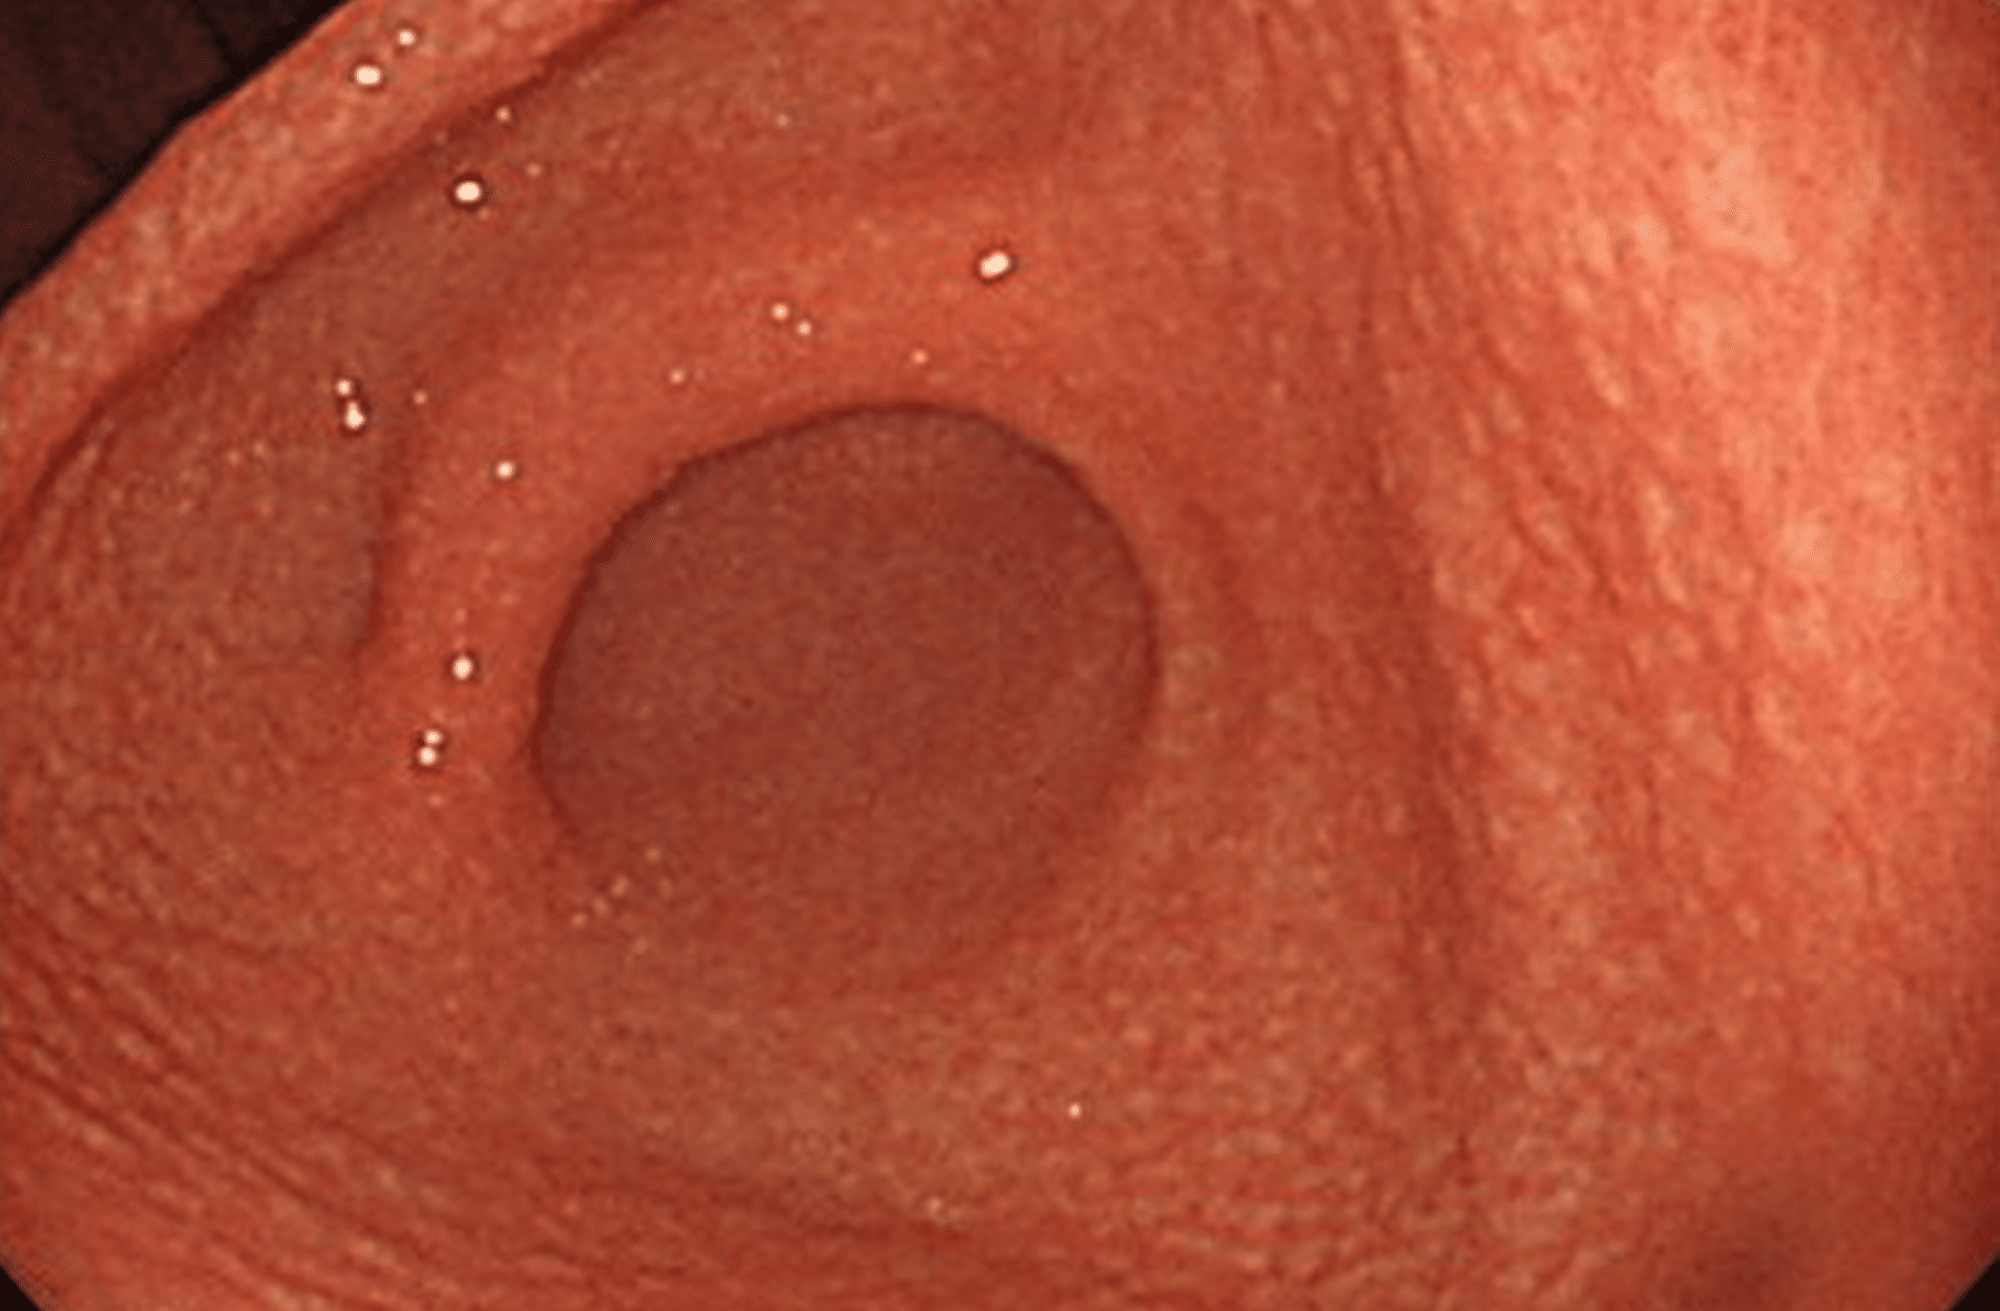

逆流性食道炎

胸焼けや胃もたれ、呑酸、喉の違和感、咳などの症状がみられます。重症の逆流性食道炎は、食道がん発生のリスクが高くなります。